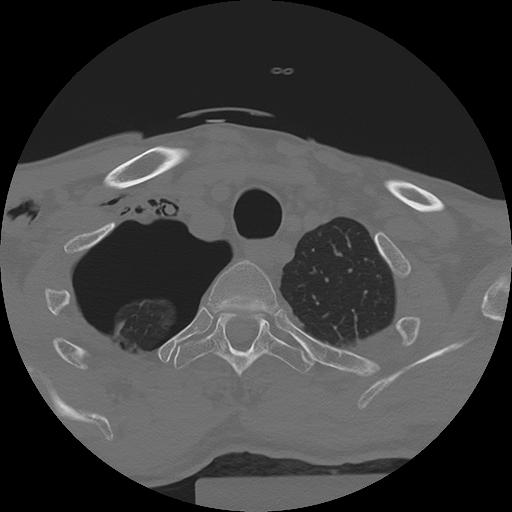

11 HUESO,,Axial,2.0,HUESO,,